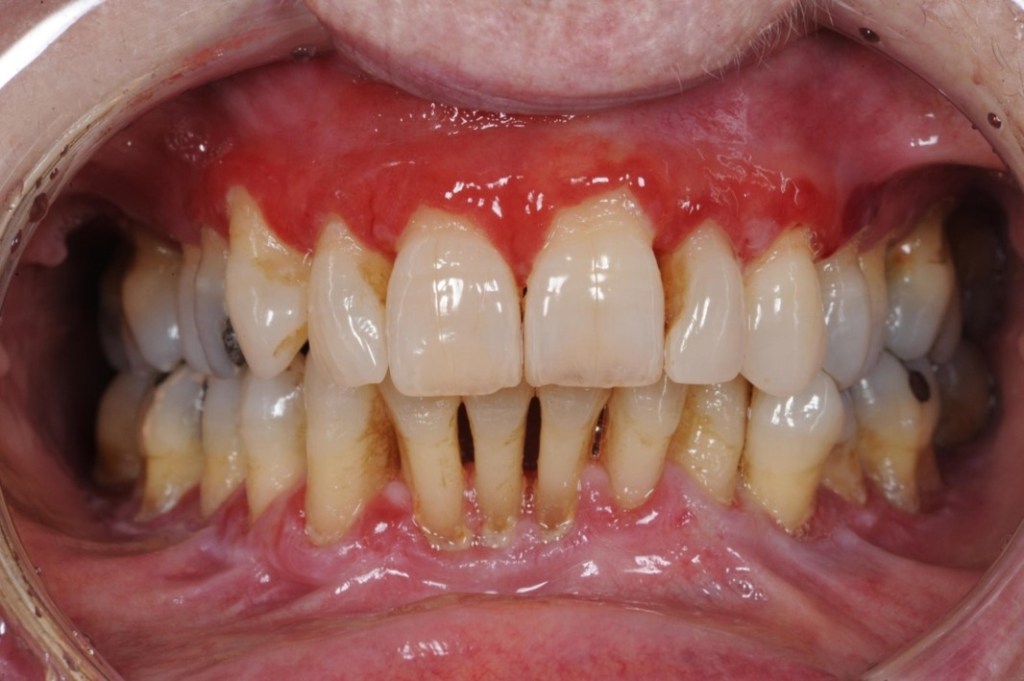

A recent study from the University of Birmingham suggests that Kidney disease patients with gum disease have greater mortality risk.

Severe gum disease increases the risk of death from chronic kidney disease by ten per cent, a new study suggests. Patients with chronic kidney disease (CKD) and periodontitis had a mortality rate of 41 per cent after 10 years, while those with just CKD had a 32 per cent rate. Researchers at the University of Birmingham, Praveen Sharma and Iain Chapple, said the mouth acts as a gateway for bacteria which can easily get into the blood stream through bleeding and sore gums. The study published in the Journal of Clinical Periodontology was based on data from 13,734 participants in the US-based Third National Health and Nutrition Examination Survey (NHANES III).